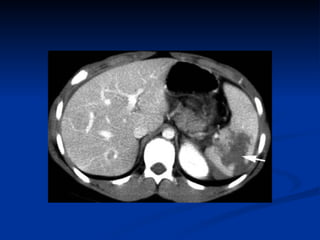

Upper Abdomen CT

Lower Abdomen CT

Techniques for Evaluation Organ Specific Dx Only CT  Also evaluates retroperitoneum Expensive Radiation Ex Lap Laparotomy gold standard for evaluation  Concomitant treatment Retroperitoneum difficult to explore/assess

Techniques for Evaluation Organ Specific Dx Only CT  Also evaluates retroperitoneum Expensive Radiation Ex Lap Laparotomy is the gold standard for evaluation  Concomitant treatment Retroperitoneum difficult to explore/assess